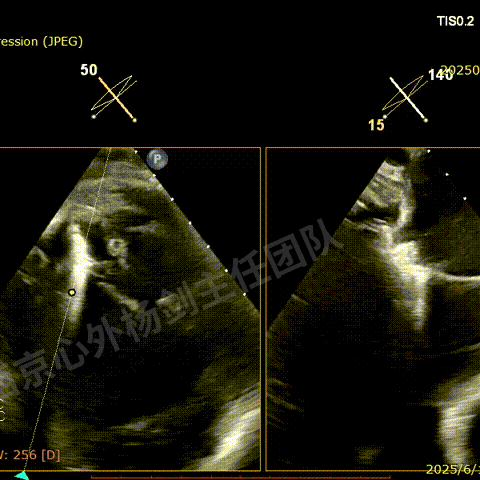

TAVR术后,全心增大,二尖瓣反流重度,三尖瓣反流重度。中量心包积液。左室严重增大,标准图像调整困难。主动脉瓣位带支架人工瓣膜瓣叶启闭正常,主动脉瓣位人工瓣上血流速度Vmax 148cm/s,PGmax 9mmHg,Vmean 86cm/s,PGmean 2mmHg, VTI 34.7cm,瓣周反流(轻)。估测肺动脉收缩压约49mmHg;左室收缩功能明显减低。LVEF:23%,EDV:364ml,ESV:221ml。

彩色血流示:二尖瓣反流缩流颈彩宽6.6mm,面积17cm²,容积30ml;二尖瓣瓣口面积6.6cm²,瓣环内径:左右径34mm,前后径34mm。2区瓣叶长度:前叶36mm,后叶20mm,叶环比1.6. 三尖反流面积17.2cm²,容积33ml,Vmax 291cm/s,PGmax 34mmHg。